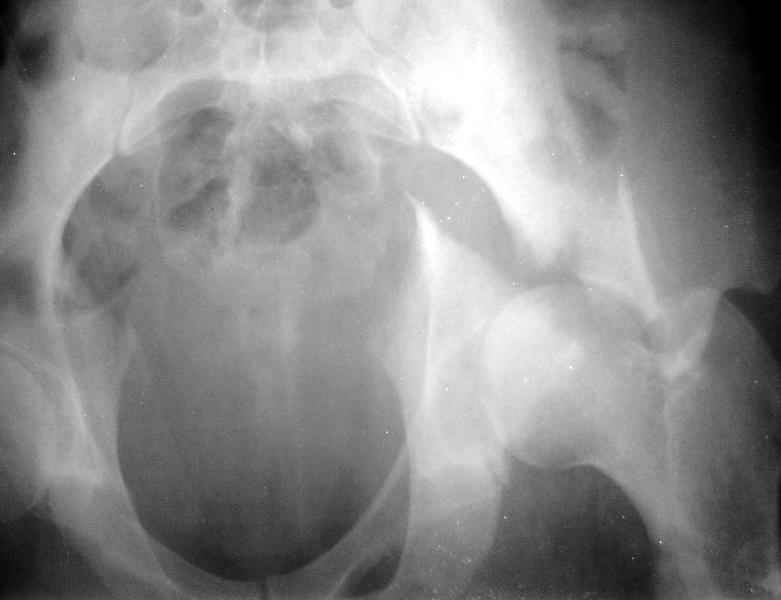

Есть такое дело. Хотя, похоже, зафиксировать здесь можно даже без специальных гвоздей для проксимального отдела. В приложении пример случая с подобным по величине центральным отломком.

Кликните для загрузки файла 1.jpg

19KB (19658 bytes)

Комментарии излишни - все ясно и без слов, качественная *сборка*.

Одним из альтернативных решений при подобном типе перелома - сверление доп. отверстия в гвозде, чтобы предовтратить излишнюю протрузию гвоздя из проксимального отломка.